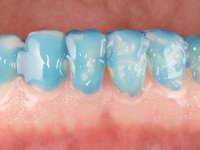

Realizado o diagnóstico e tomada a decisão quanto ao tratamento a executar, tornou-se importante definir qual a sequência de trabalho a adotar no sentido de conseguir a reabilitação da D.V.O. (V.D.O), de forma progressiva e equilibrada. Na primeira fase fez-se uma pré-impressão da arcada inferior com silicone tipo “putty” e em seguida realizou-se o preparo dentário de todo o sector posterior. O preparo para os overlays foi feito coronalmente à linha amelo cementaria no sentido de ser o mais conservador possível. A impressão foi feita com técnica de dupla mistura após afastamento gengival realizado com pasta de caulino. A provisória foi realizada com resina composta de polimerização dual. Em laboratório foram realizados os overlays após se ter aberto ligeiramente (1,5mm) a D.V.O. nos modelos montados em articulador semi-ajustável. Simultaneamente o sector antero-inferior foi encerado no sentido de acompanhar este aumento da D.V.O. Também foi confecionada uma chave de silicone translucido para posterior confeção dos provisórios antero-inferiores. Em boca foi primeiro realizada a provisionalização dos dentes anteriores utilizando resina composta previamente aquecida após preparação das superfícies dentárias para a adesão. Foi colocado o dique de borracha para promover o isolamento absoluto e posteriormente foram colados os overlays. Em laboratório foi realizada nova chave de silicone para confecionar os provisórios antero-superiores. Seguidamente em boca foram preparados os seis dentes antero-superiores após colocação do fio de afastamento gengival. Feita a preparação adequada das superfícies dentárias foi realizada a impressão com técnica de dupla mistura e a respetiva provisória. Em laboratório foram confecionadas 6 facetas feldespáticas num modelo de trabalho tipo “Geller”. A provisória foi removida e as facetas foram coladas em boca utilizando um isolamento relativo competente. Esta opção foi tomada em virtude de uma prévia experiencia negativa com a colocação do dique de borracha na mandibula. Após a colagem dos laminados antero-superiores foram dadas 12 semanas para avaliar a adaptação do paciente à nova situação e então iniciar a confeção das facetas antero-inferiores. Após colocação do fio de afastamento gengival. foram feitos os preparos dentários adequados e em seguida foi feita a impressão. Também foi feita a preparação do dente 3.4 que, entretanto, tinha sofrido uma fratura do overlay. As facetas e a restauração do 3.4 foram realizadas num modelo de trabalho tipo “Geller”. Após remoção da provisória, as facetas foram coladas em boca, utilizando um isolamento relativo pelas razões apontadas anteriormente. Após colocação do trabalho o paciente foi reabilitado por outros colegas com um implante na zona do 2.6 e substituição da coroa aparafusada sobre o implante colocado no local do 3.5. Posteriormente surgiram fraturas nos overlays dos dentes 4.7 e 3.7 que foram reabilitados com overlays em Zr.